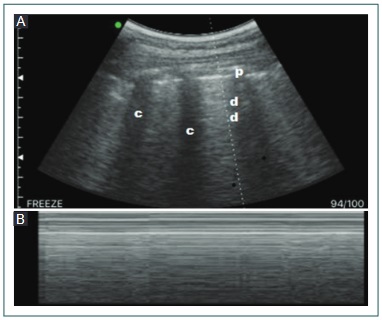

3) Línea pleural: se observa perpendicular entre dos sombras acústicas generadas por la costilla superior e inferior, conocido como el «signo del murciélago». La línea pleural se visualiza como una banda hiperecogénica, de hasta 2 mm de grosor normalmente. Durante los movimientos respiratorios, esta línea tiene un movimiento ondulante hacia delante y atrás respecto a la pared torácica, que representa el movimiento de la pleura visceral contra la parietal, conocido como el «signo de deslizamiento pulmonar», que en modo M se describe como el «signo de la playa»; esto observado en las zonas anterior y anteromedial de cada zona explorada (Fig. 1).

Imagen normal. A: modo bidimensional. B: modo M: «signo de la playa». c: sombra costal; d: líneas A; p: línea pleural.